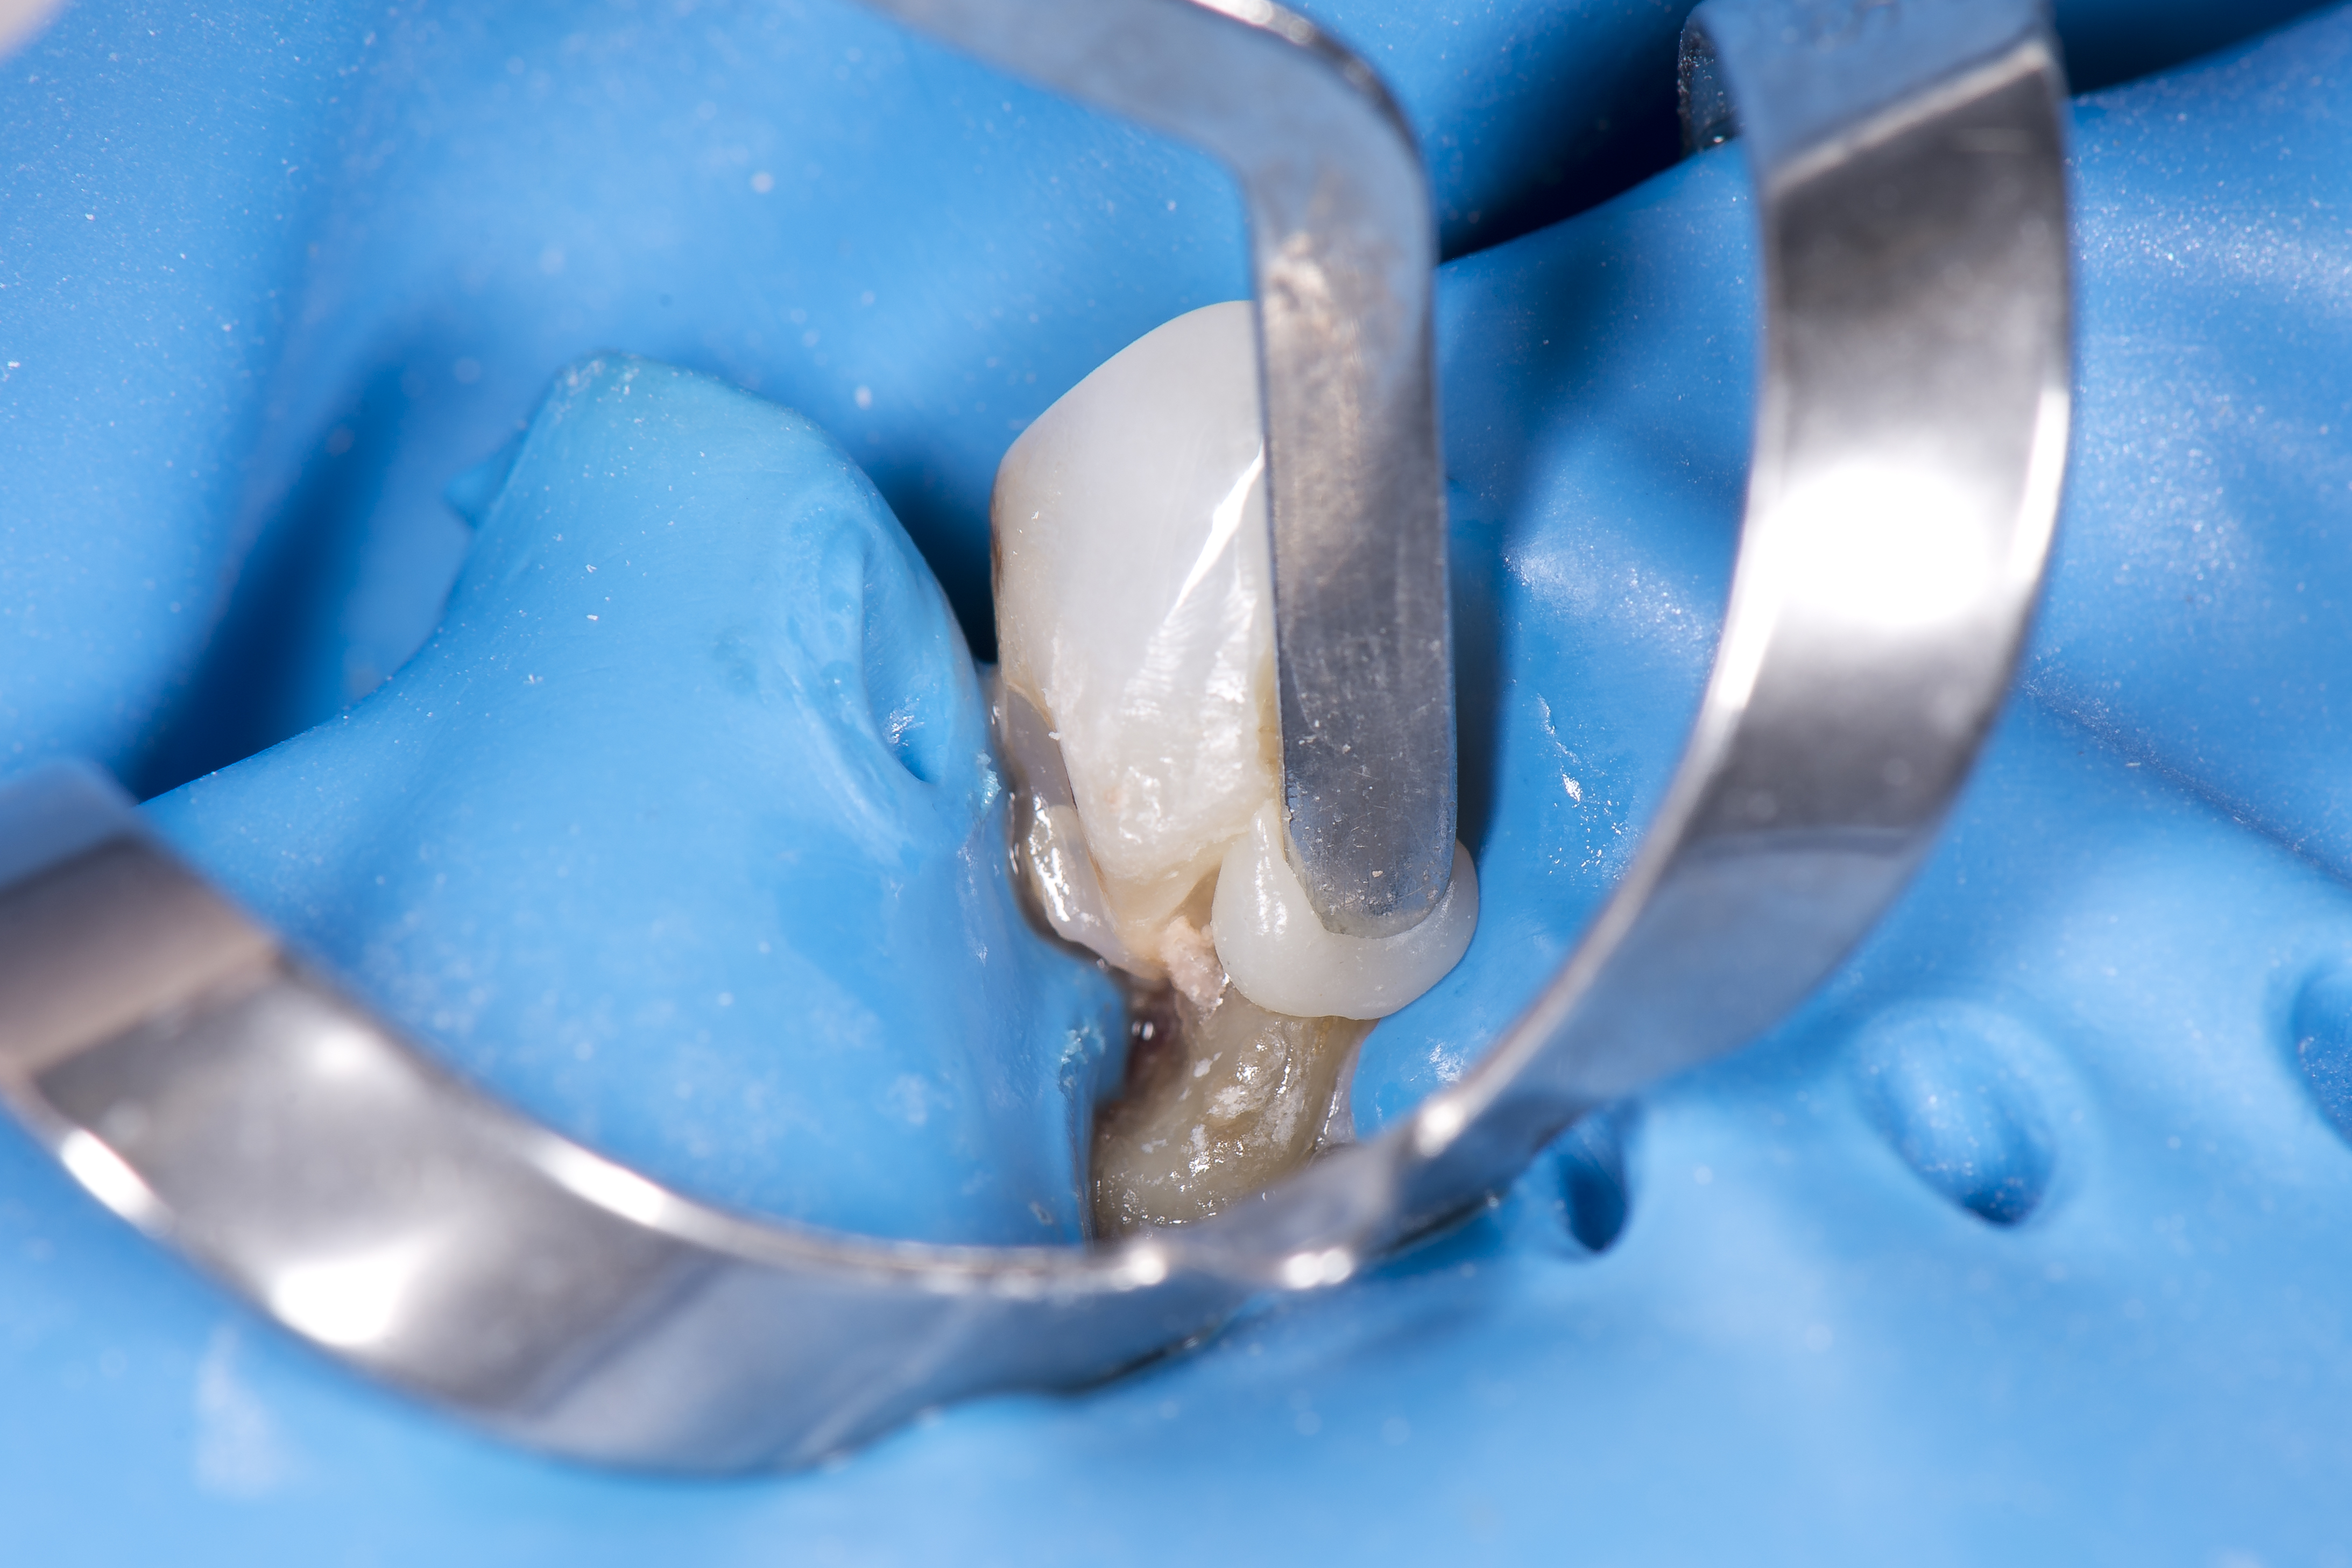

W ciągu kilku kolejnych wizyt przeprowadzono leczenie zachowawcze w obrębie zębów, związane z preparacją kolejnych ubytków próchnicowych i ich wypełnianiem. Objęło ono: ubytek klasy III M i D w zębie 11, ubytek klasy III M i D w zębie 21, ubytek klasy III M i V w zębie 22, oraz ubytek klasy V okrężny w zębie 23. Zastosowano materiał kompozytowy OptiShade (Kerr) w odcieniu MEDIUM w przypadku wszystkich wypełnień. Procedura kliniczna w każdym przypadku wyglądała tak samo (ryc. 6).

Ryc. 6. Stan po wypełnieniu ubytków klasy III mezjalnie i dystalnie w zębach 11, 21 materiałem OptiShade Medium (Kerr).

Ząb był izolowany przy pomocy koferdamu OptiDam (Kerr) i dokonano preparacji ubytku próchnicy pierwotnej lub też usunięto nieszczelne wypełnienie kompozytowe – w przypadku zębów 22 i 23 były to wypełnienia klasy V, pod którymi zaczęła rozwijać się próchnica okrężna obejmująca powierzchnię korony zęba i korzenia (ryc. 7).

Był on nakładany w porcjach, których grubość nie przekraczała 2 mm i polimeryzowany przez 20 sekund (ryc. 11).

Ryc. 11. Zastosowano odbudowę warstwową przy użyciu tylko jednego odcienia materiału.